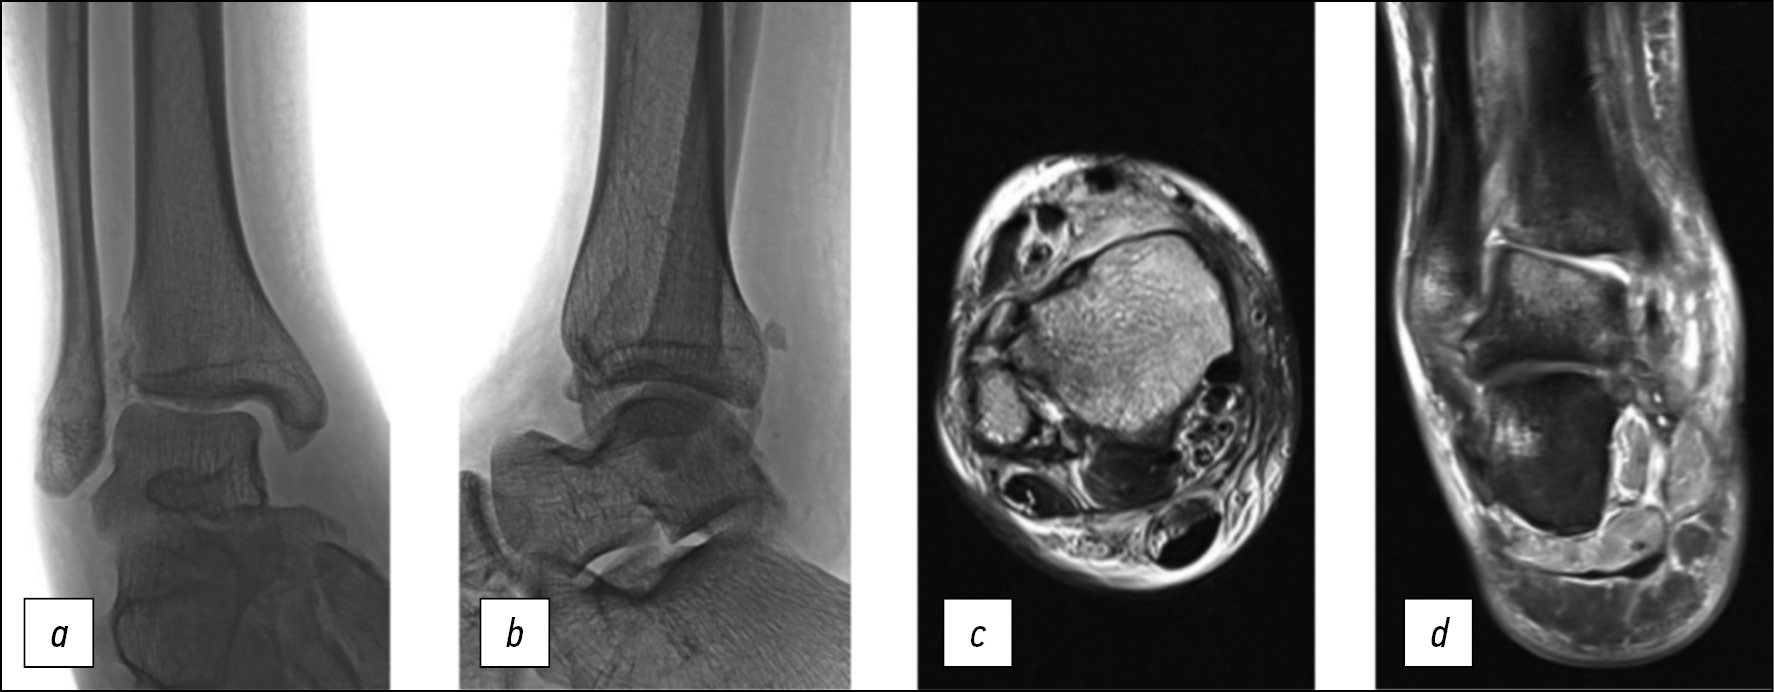

На магнитно-резонансных томограммах (МРТ) правого голеностопного сустава во фронтальной плоскости в режиме Т1 наблюдаются несросшийся перелом внутренней лодыжки, разрыв поверхностной (рис. 1a) и глубокой (рис. 1b) порций внутренней коллатеральной связки. На компьютерной томограмме (КТ) правого голеностопного сустава в кософронтальной плоскости (рис. 1c) наблюдаются консолидированный со смещением отломков по ширине перелом дистальной трети диафиза малоберцовой кости, несросшийся перелом внутренней лодыжки, подвывих стопы кнаружи. На МРТ правого голеностопного сустава в аксиальной плоскости в режиме Т2 наблюдаются разрыв передней и задней межберцовых, межкостной связок с признаками рубцевания, латеропозиция наружной лодыжки относительно малоберцовой вырезки большеберцовой кости (рис. 1d), разрыв глубокой порции дельтовидной связки с признаками рубцевания (рис. 1e).

Рис. 1. a, b — магнитно-резонансные томограммы пациентки В. на момент поступления во фронтальной плоскости в режиме Т1, c — компьютерная томограмма в кософронтальной плоскости, d, e — магнитно-резонансные томограммы в аксиальной плоскости в режиме Т2

Fig. 1. a, b — preoperative coronal T1 magnetic resonance imaging of patient B., c — oblique-frontal plane computed tomography scan, d, e — axial T2 magnetic resonance imaging